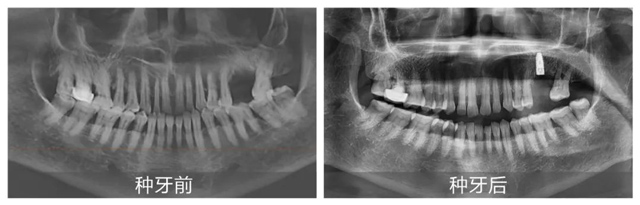

在李丹主任細致講解的同時,手術室已準備就緒,上午10:32分,手術正式開始。從術前消毒到定量麻醉,從定點備洞到精準植入,再到最后的嚴密縫合,黃杰醫生始終有條不紊地依序進行。手術全程都由李丹主任與吳海燕主管同步配合講解,現場觀眾紛紛對黃杰醫生的精湛技術拍手稱贊。

上午10:42分,黃杰醫生與手術顧客一同向鏡頭揮手,示意手術完成。僅花費10分鐘,李女士便實現了落齒重生。隨后,黃杰醫生與李女士也在如潮的掌聲中重返直播現場。